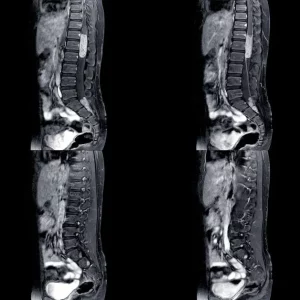

The spinal cord uses neural pathways to communicate with the brain and muscles. When neural pathways become damaged or destroyed by a spinal cord injury, it can result in loss of sensation, immobility, and other secondary effects.

In a complete injury, the spinal cord is fully severed; meaning there are no existing neural pathways below the level of injury. However, with an incomplete injury the spinal cord is only partially severed and there are spared neural pathways remaining. Spared neural pathways can be strengthened by neuroplasticity, the nervous system’s ability to heal and rewire itself.

The level of spinal cord injury (the lowest region where movement and sensation exist) determines which muscles and neural pathways are recoverable. Neuroplasticity strengthens existing neural pathways and creates new ones, allowing for better communication between the central nervous system and the body.